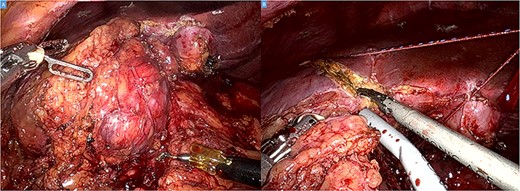

The operation was performed using the Da Vinci Xi system. Initial exploration showed a large and bulky lesion in the liver’s segments V–VI completely fused to the right colonic flexure (Fig. 3A and B).

Intraoperative picture showing a bulky tumor infiltrating the liver’s segments V–VI and the right colic flexure (A). Hepatic transection with the harmonic (B).

The ascending colon and hepatic flexure were detached. The mesocolon was divided, and the ascending and proximal transverse colon were transected with the stapler leaving the right hepatic flexure attached to the tumor. Before the hepatic transection, intraoperative ultrasound was performed to confirm the tumor position, plan the resection line and rule out other nodules. Intestinal continuity restoration was achieved with a side-to-side anastomosis. Finally, the specimen was retrieved through a Pfannenstiel incision.